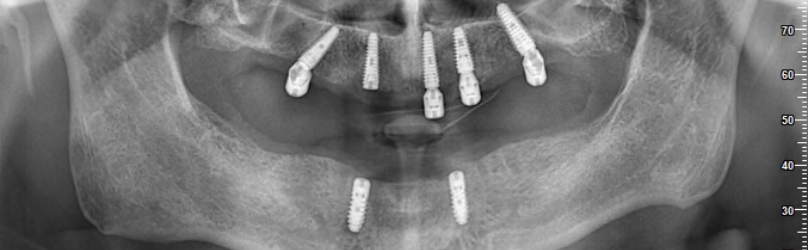

La première étape du processus de traitement consiste à prendre des images radiographiques détaillées. Ces images aident à déterminer le plan de traitement le plus approprié en évaluant la structure de votre mâchoire et votre santé dentaire. Nos radiographies révèlent à quel point le processus de traitement est extrêmement minutieux.

Dans les étapes ultérieures, vous pouvez regarder des vidéos sur la façon de placer des implants et de produire des prothèses. Ces vidéos visent à fournir une perspective informative à nos patients en montrant chaque étape du processus. Chaque étape est réalisée minutieusement par nos médecins experts.